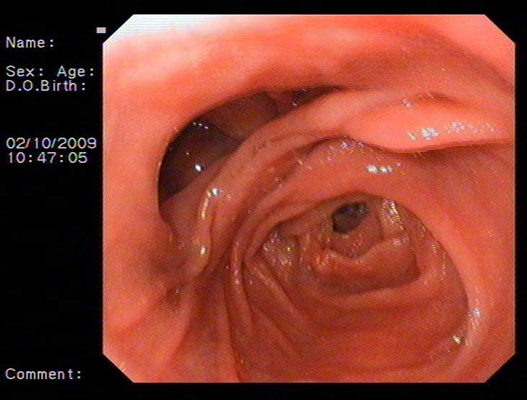

食道炎圖片